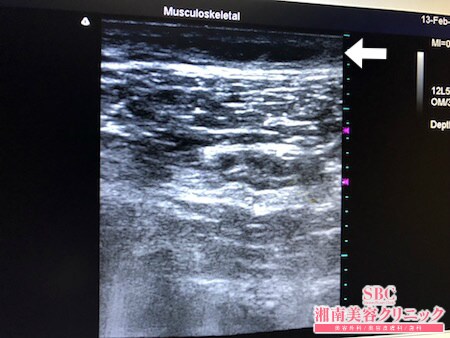

No.226808【脂肪吸引】【動画あり】湘南美容外科全ドクターの脂肪吸引最高責任者である竹田先生による脂肪吸引のフォトギャラリー!他院の再手術!もうひと絞りを根こそぎ竹田先生にお願いする!術中3Dタッチビュー・左太もも後面